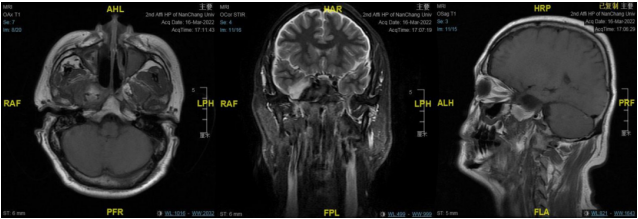

右侧鞍旁见类圆形占位,中央稍低密度,周围环形稍高密度,可见残留骨质密度影,大小约 32☓46 mm,邻近骨质吸收变薄,建议 MRI 平扫+增强扫描。

右侧中颅窝鞍旁见一大小约 34 mm✕40 mm✕47 mm 肿块,信号混杂,T1、T2 均呈等低高混杂信号,DWI 呈不均匀混杂信号,边缘包膜呈稍长 T1 短 T2 信号,肿块边界清;肿块无强化,边缘包膜呈明显强化。

中颅窝右侧鞍旁可见无强化稍低密度影,边缘可见少许钙化影,边界清晰,邻近骨质受压变薄,邻近颈内动脉受压内移。

结合此病例影像学特点:T1、T2 均呈等低高混杂信号,肿块边界清;肿块无强化,边缘包膜呈明显强化。

从 MRI 增强扫描上肿块无强化,可与神经鞘膜瘤相鉴别;CTA 成像无强化环及强化结节表现,肿块将颈内动脉向后推挤,MRI 增强也无病变周边高信号环及典型的动脉搏动伪影表现,这些影像学表现上可与动脉瘤相鉴别。